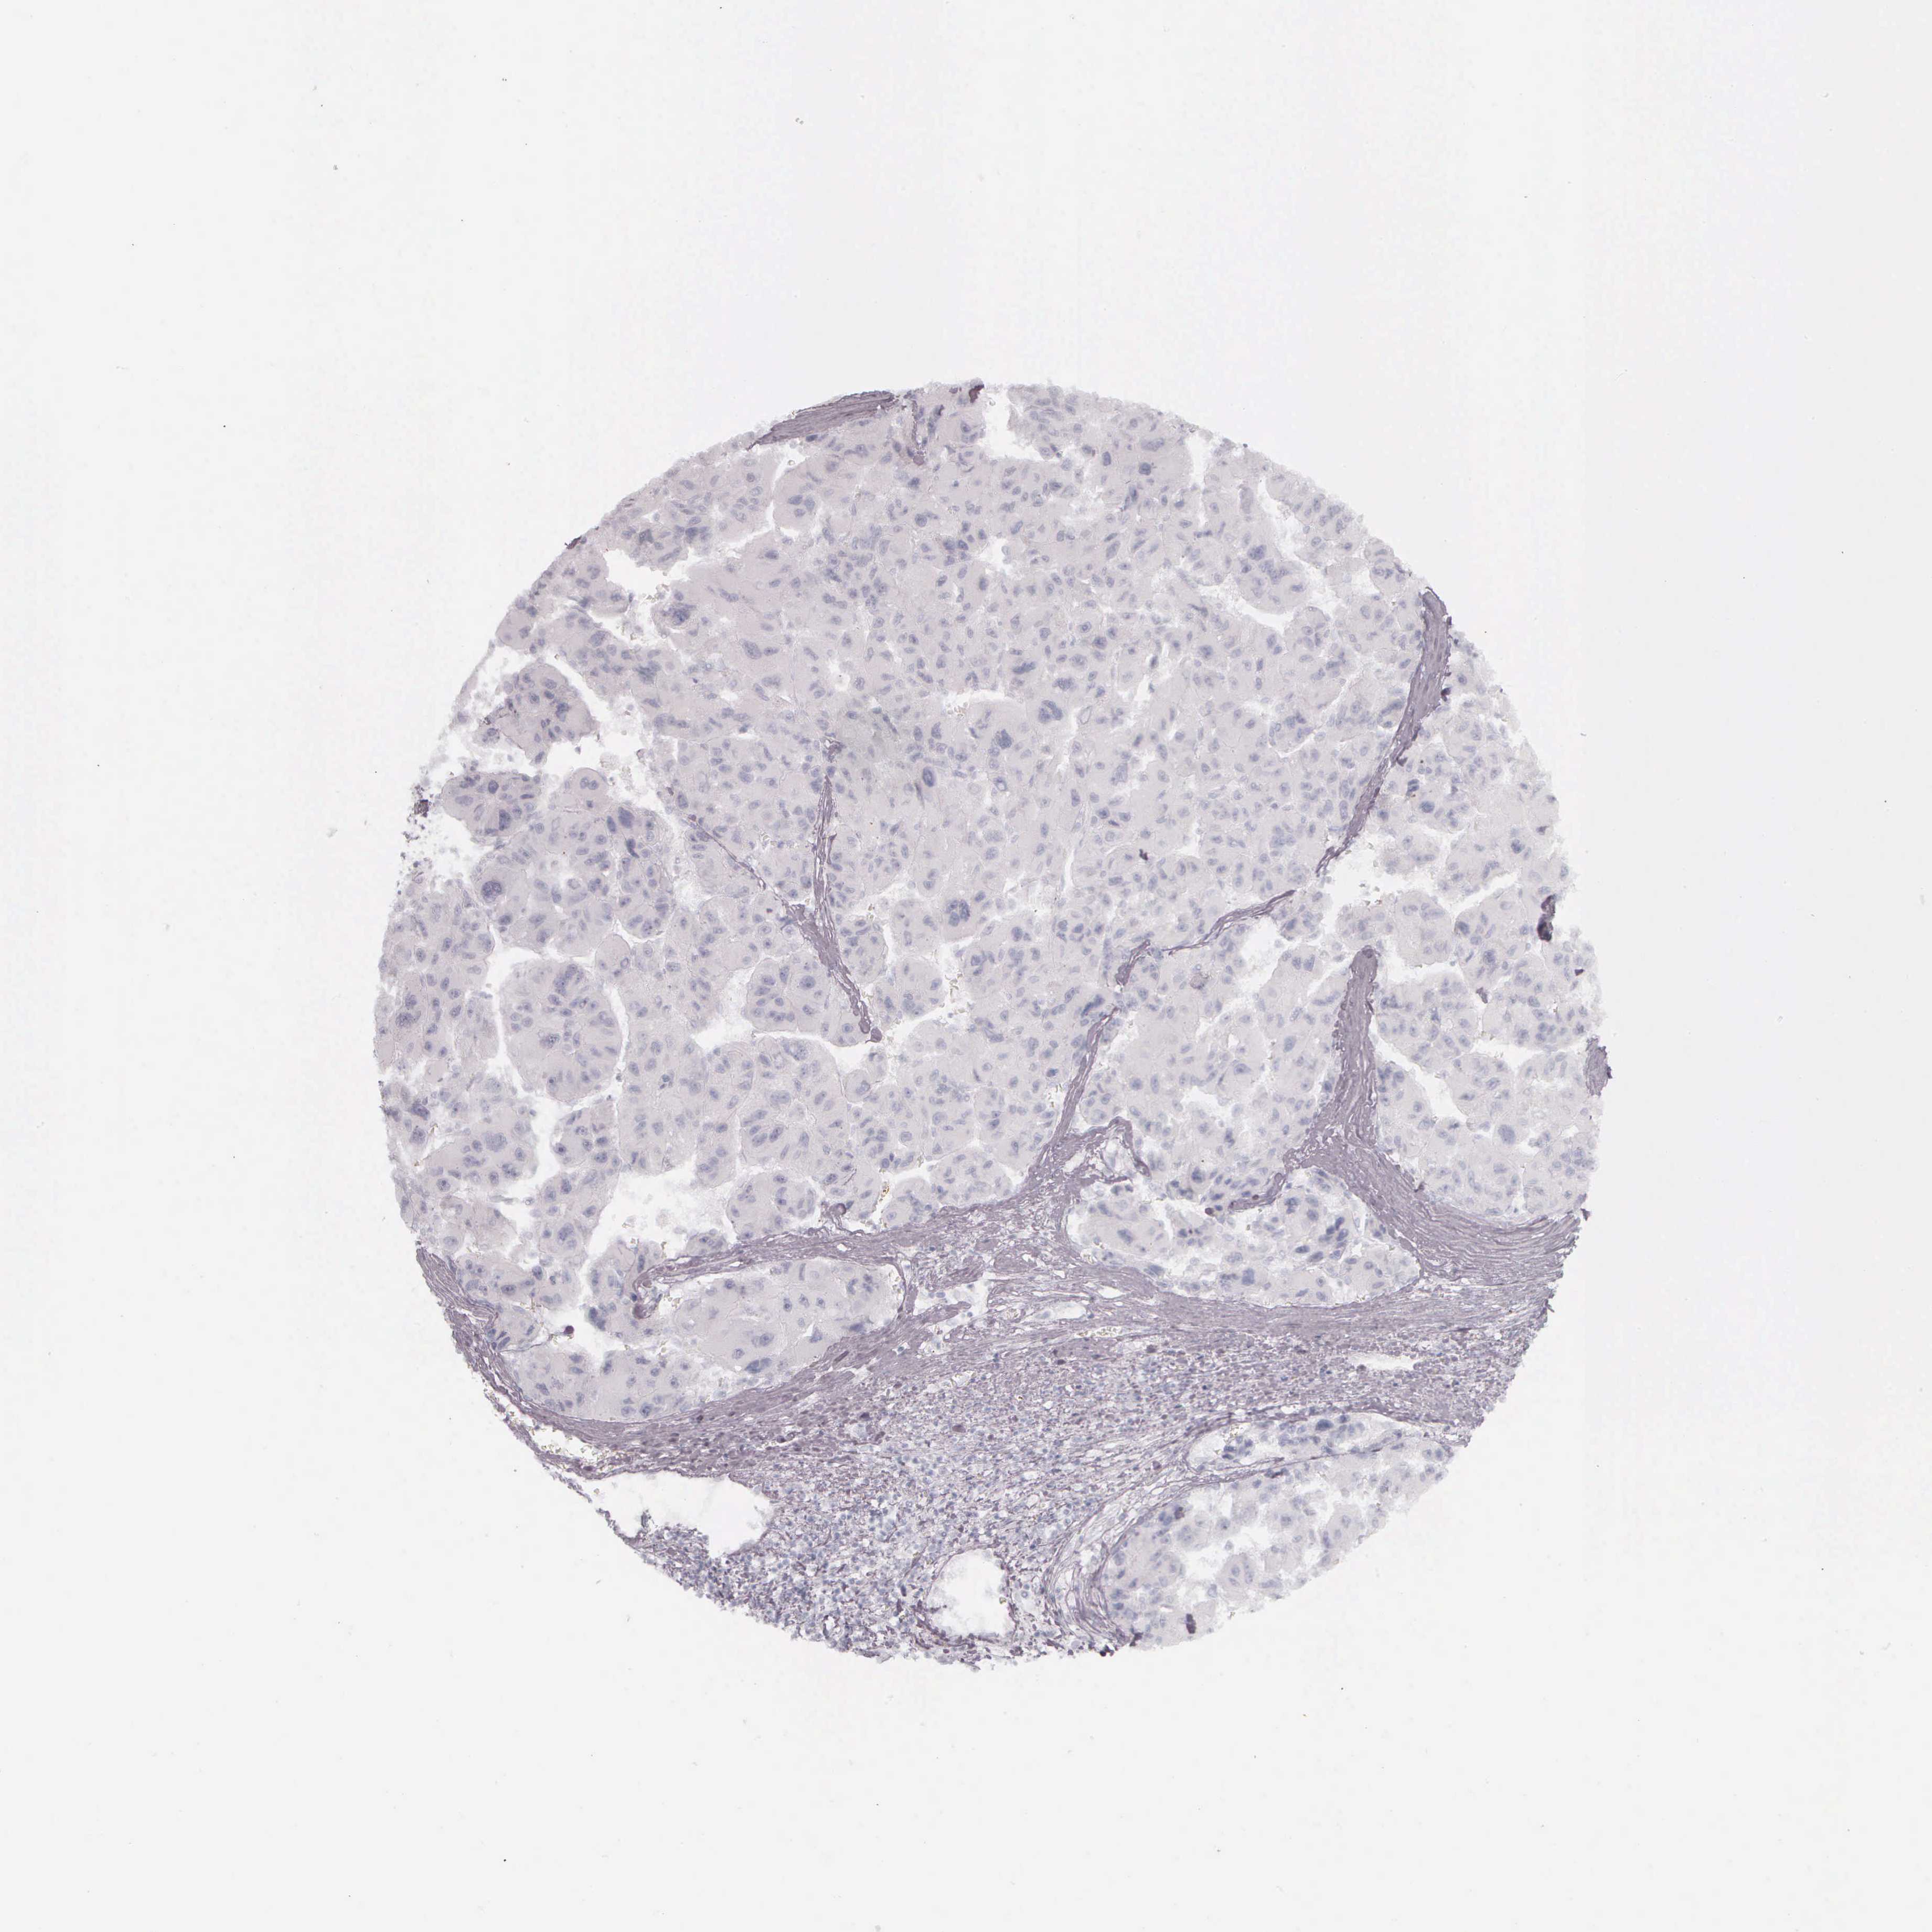

LIVER CANCER - Protein expressioni

A mouse-over function shows sample information and annotation data. Click on an image to view it in a full screen mode. Samples can be filtered based on level of antibody staining by selecting one or several of the following categories: high, medium, low and not detected. The assay and annotation is described here.

Note that samples used for immunohistochemistry by the Human Protein Atlas do not correspond to samples in the TCGA dataset.

Antibody stainingi

Antibody staining in the annotated cell types in the current human tissue is reported as not detected, low, medium, or high, based on conventional immunohistochemistry profiling in selected tissues. This score is based on the combination of the staining intensity and fraction of stained cells.

Each image is clickable and will lead to virtual microscopy that enables deeper exploration of all samples and also displays staining intensity scores, fraction scores and subcellular localization as well as patient and tissue information for each sample.

Antibody HPA000452

Antibody HPA023040

Antibody CAB000134

Carcinoma, Hepatocellular, NOS